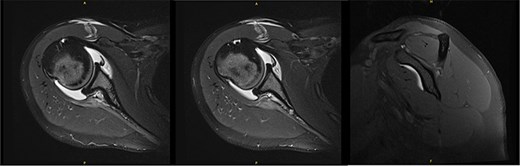

New MRI arthrogram demonstrated no evidence of new or worsening SSN compression or other pathology. Imaging demonstrated increased right infraspinatus muscular tissue (Fig. 5), however, with significant continued fatty infiltration and persistent atrophy compared to the contralateral side.

MRI at 9.5 years after decompression demonstrated increased right infraspinatus muscular tissue.

Ten years after initial presentation, the patient returned with increased right shoulder pain after overhead injury at the gym. Her exam included a positive O’Brien’s test, and external rotation weakness. Interval EMG was normal; MRI demonstrated mild supraspinatus tendinosis, and infraspinatus atrophy with unchanged fatty infiltration (Fig. 6). The patient’s pain was hypothesized to be due to infraspinatus atrophy and overuse of other rotator cuff musculature. She elected to manage her symptoms with self-directed therapy.

MRI at final follow-up demonstrated mild supraspinatus tendinosis, and infraspinatus atrophy with continued significant fatty infiltration, unchanged from prior imaging.